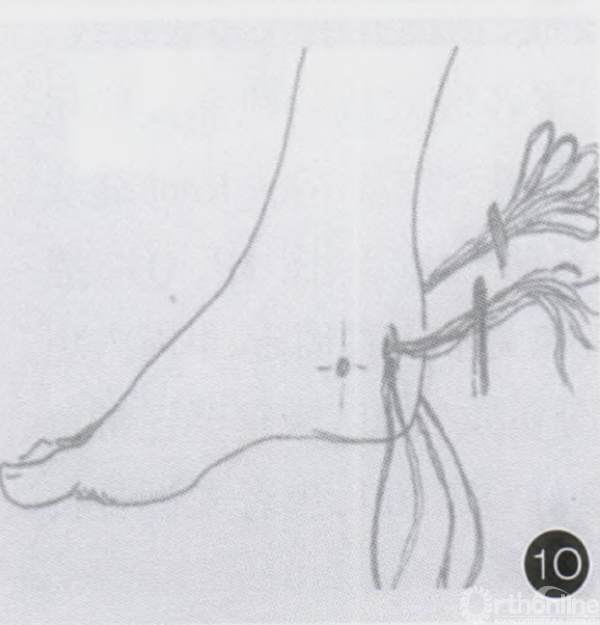

术前X片和示意图示右侧跟骨撕脱(A,B)

打紧线结,将跟骨撕脱骨折块固定示意图(Q)